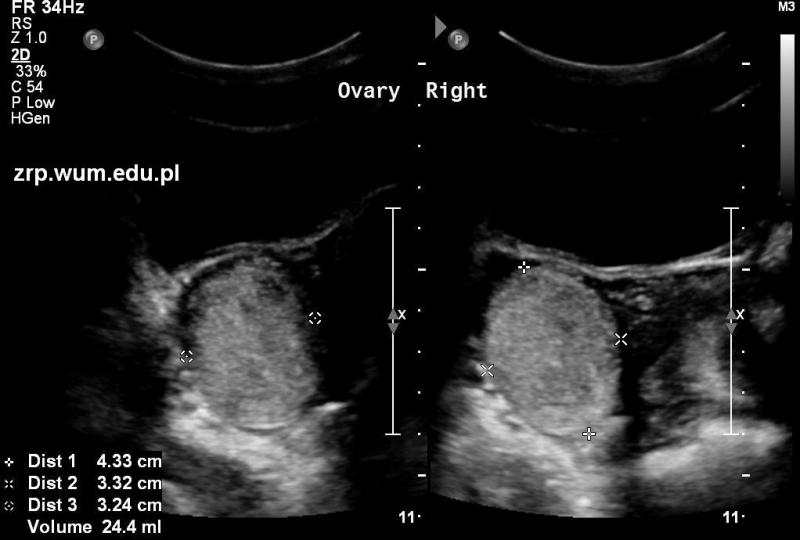

Przypadek 19: 12-letnia pacjentka zgłosiła się do IP z powodu bólu brzucha, lokalizującego się w prawym dole biodrowym. Nie gorączkowała, nie wymiotowała. Ostatnia miesiączka przed 5. tygodniami.

Rozpoznanie: Prawy jajnik powiększony (24ml, pomiary między kursorami), w całości hiperechogenny. Lewy jajnik i macica prawidłowe. Wyrostek robaczkowy bez cech zapalenia.

Pytanie: W diagnostyce różnicowej należy uwzględnić przede wszystkim torbiel krwotoczną jajnika oraz potworniaka. Jakie jest dalsze postępowanie diagnostyczne? Czy pacjentka wymaga pilnej diagnostyki / leczenia operacyjnego?